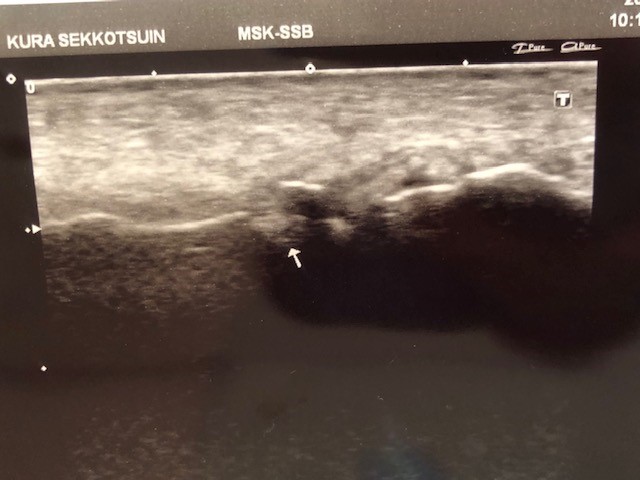

念の為エコー(超音波画像観察装置)で確認してみると、骨が折れている可能性が・・・・・

紹介状を持って普段からお世話になっている病院へ行ってもらうと骨折の診断でした。